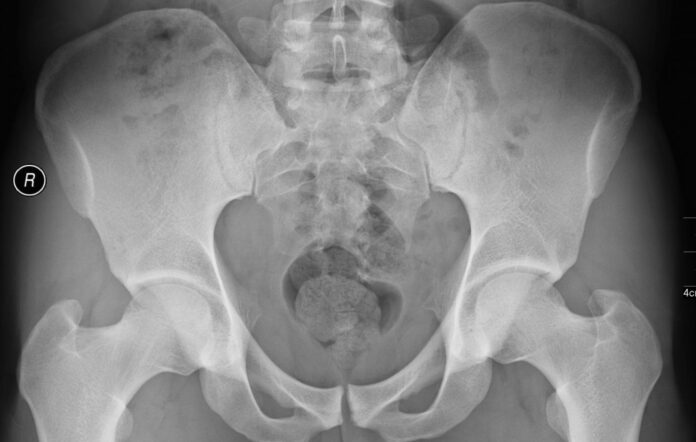

Çoğunlukla ilk olarak röntgen filmi çekilmelidir

Hastalığın tanısı hasta öyküsü ve fiziki muayene ile konulur.Ancak diğer kalça eklemi hastalıklarından olup olmadığına ayırıcı tanı yapmak için çoğunlukla ilk olarak röntgen filmi çekilmelidir. Bazı özel durumlarda ise MR ve bilgisayarlı tomografi incelemesi gerekli görülebilir.